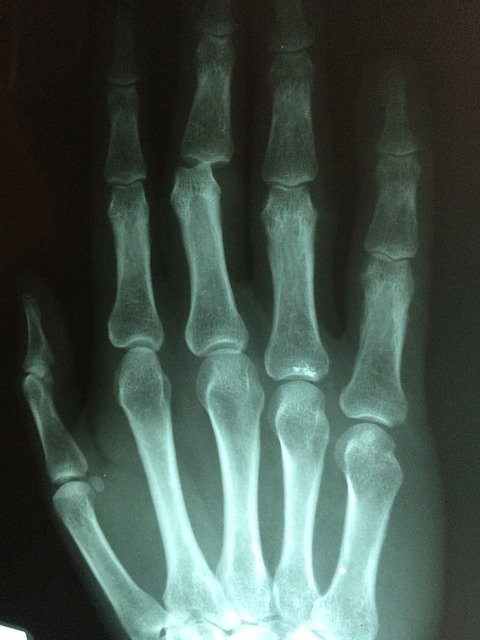

손가락 마디 통증 원인 두 번째 퇴행성 관절염은 나이가 들면서 연골이 닳거나 손상 또는 퇴행성 변화로 관절을 이루는 뼈와 인대가 손상되어 염증이 생겨서 손가락 마디에 통증을 유발합니다. 대부분 나이가 들면서 많이 발생하는대요 연골이 오랜 세월 동안 닳아서 손상되기 때문에 노년층분들의 고질병중 하나로 꼽힙니다. 퇴행성 관절염의 경우 손가락 마디 통증에서 그치지 않고 무릎관절 팔꿈치 등 연골이 손상된 경우 통증을 느낍니다.

손가락 마디 통증 원인 세 번째 류마티스 관절염은 정확한 원인은 밝혀지지 않았지만 면역력 문제로 많이 발생한다고 알려져 있습니다. 다른 원인으로는 세균 감염 바이러스 등이 있습니다. 육체적으로 무리를 하거나 스트레스를 많이 받는 경우 발병률이 높아지는 것으로 알려져 있습니다. 증상으로는 피고 감 식욕부진 무력 감등이 있습니다. 류마티스 관절염의 경우 아침에 일어났을 때 관절염이 더 심해집니다. 손가락이 뻣뻣해지거나 통증이 1시간가량 지속되는 경우 류마티스 관절염이 의심되므로 필히 병원에 방문하여야 합니다. 방치할 경우 손가락에 변형이 생길 수 있습니다.